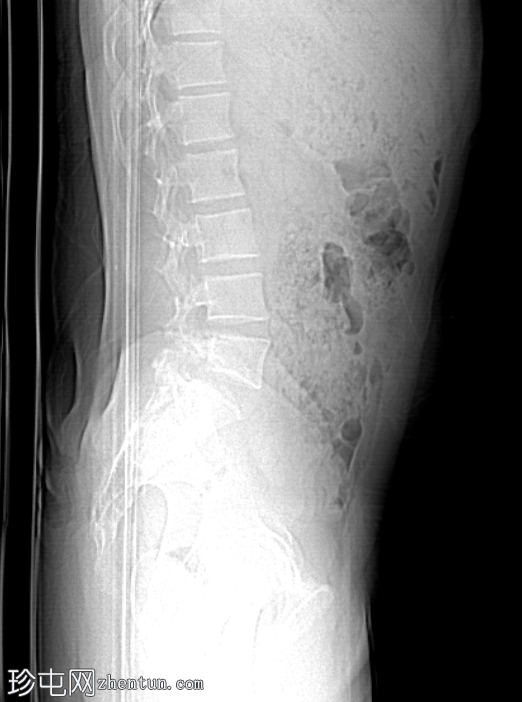

前后位-侧位

定位像